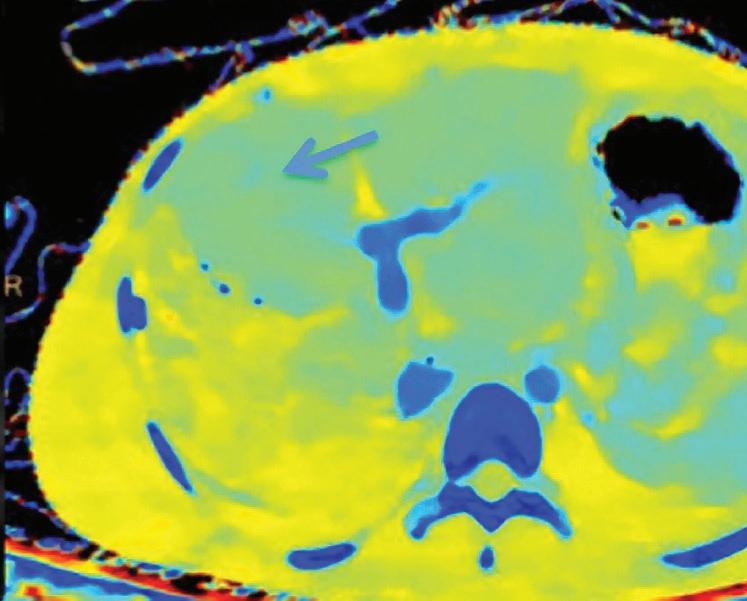

Patient presented to the emergency department with abdominal pain. The conventional CT does not reveal any abnormality in the gallbladder. In the middle row, spectral attenuation curves reveal two different materials: a first region of interest (purple) with a CT number that is increasing with energy, typical of a low Z effective element (below the Z effective value of water), and a second region of interest (blue) with a CT number that is decreasing with the energy, typical of a Z effective above water. The differentiation between the two materials cannot be performed based on the conventional CT because the two attenuation curves cross each other around 70 keV (where the attenuation is equivalent to the conventional CT). The lower row displays spectral results in the Magic Glass, from left to right: 40 keV image, 200 keV image, iodine density image, and Z effective map. A gallstone is clearly revealed on the 40 keV image and with an inverted contrast on the 200 keV image. The iodine density shows a perfusion defect of the gallbladder wall due to the compression with the gallstone (white arrow), and the Z effective helps us to determine the gallstone composition with a Z effective below 6.5 typical of a cholesterolic composition.